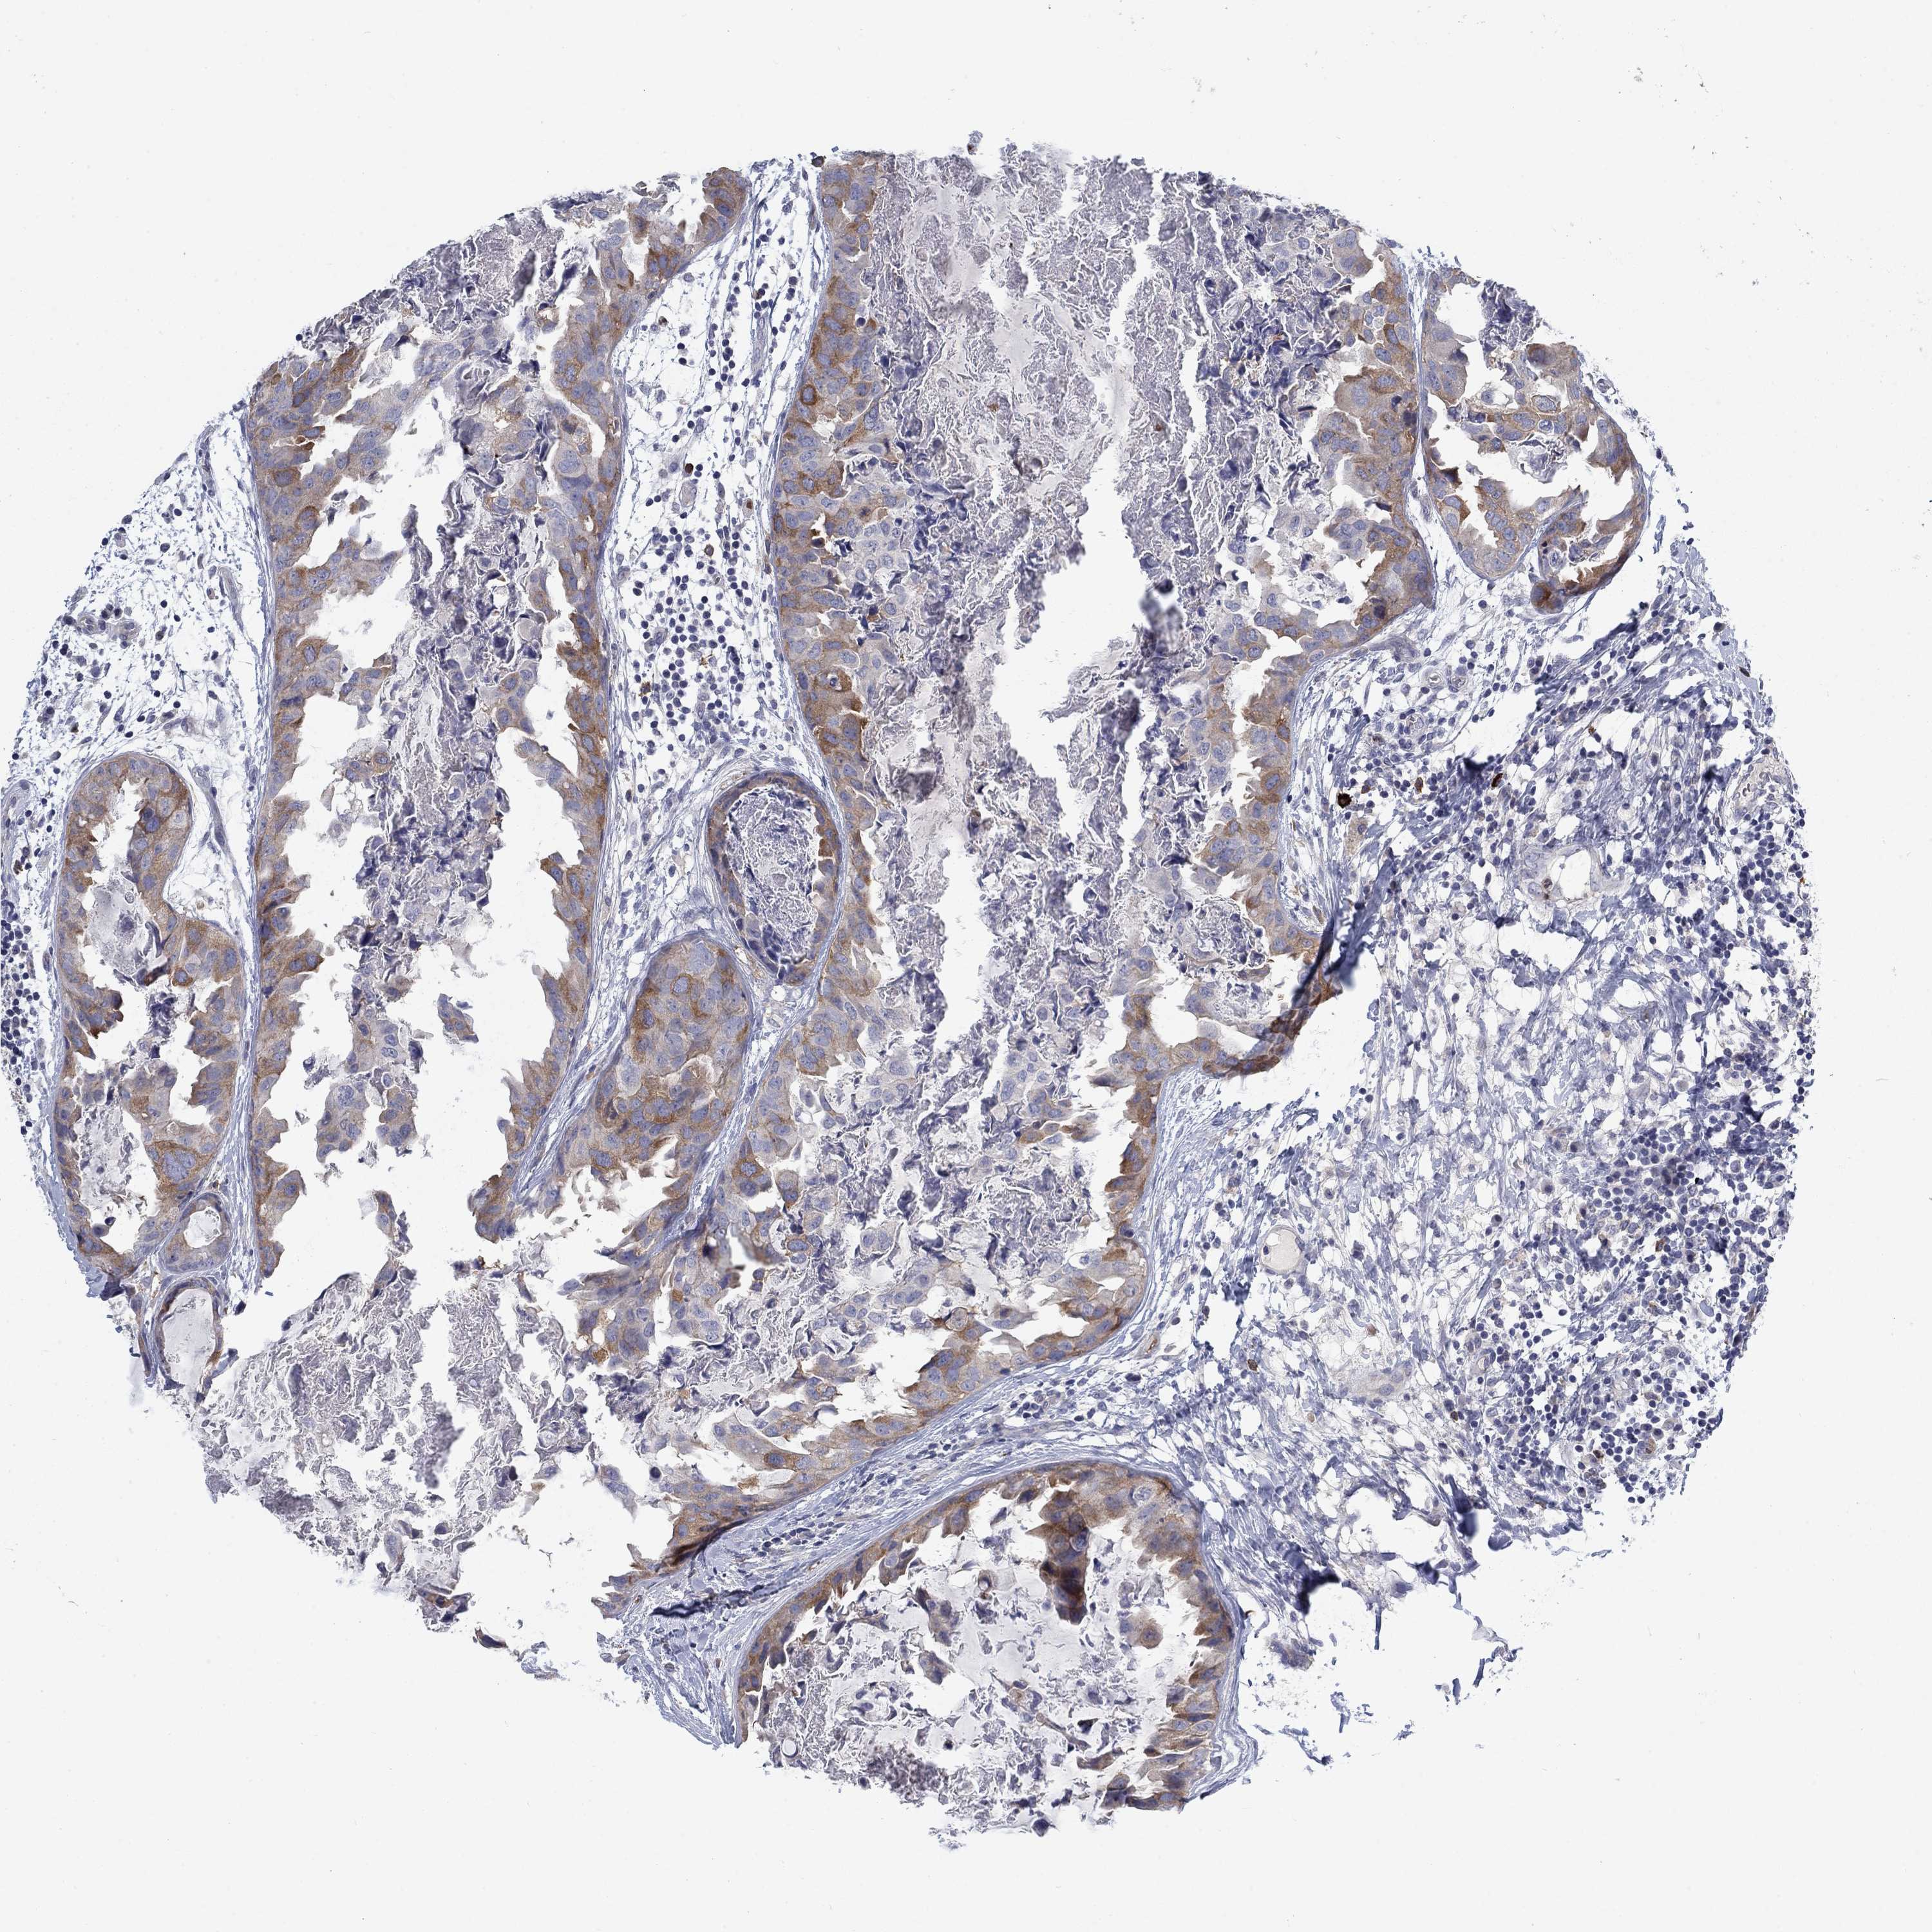

BRCA TCGA BRCA VALIDATION PROTEIN EXPRESSION